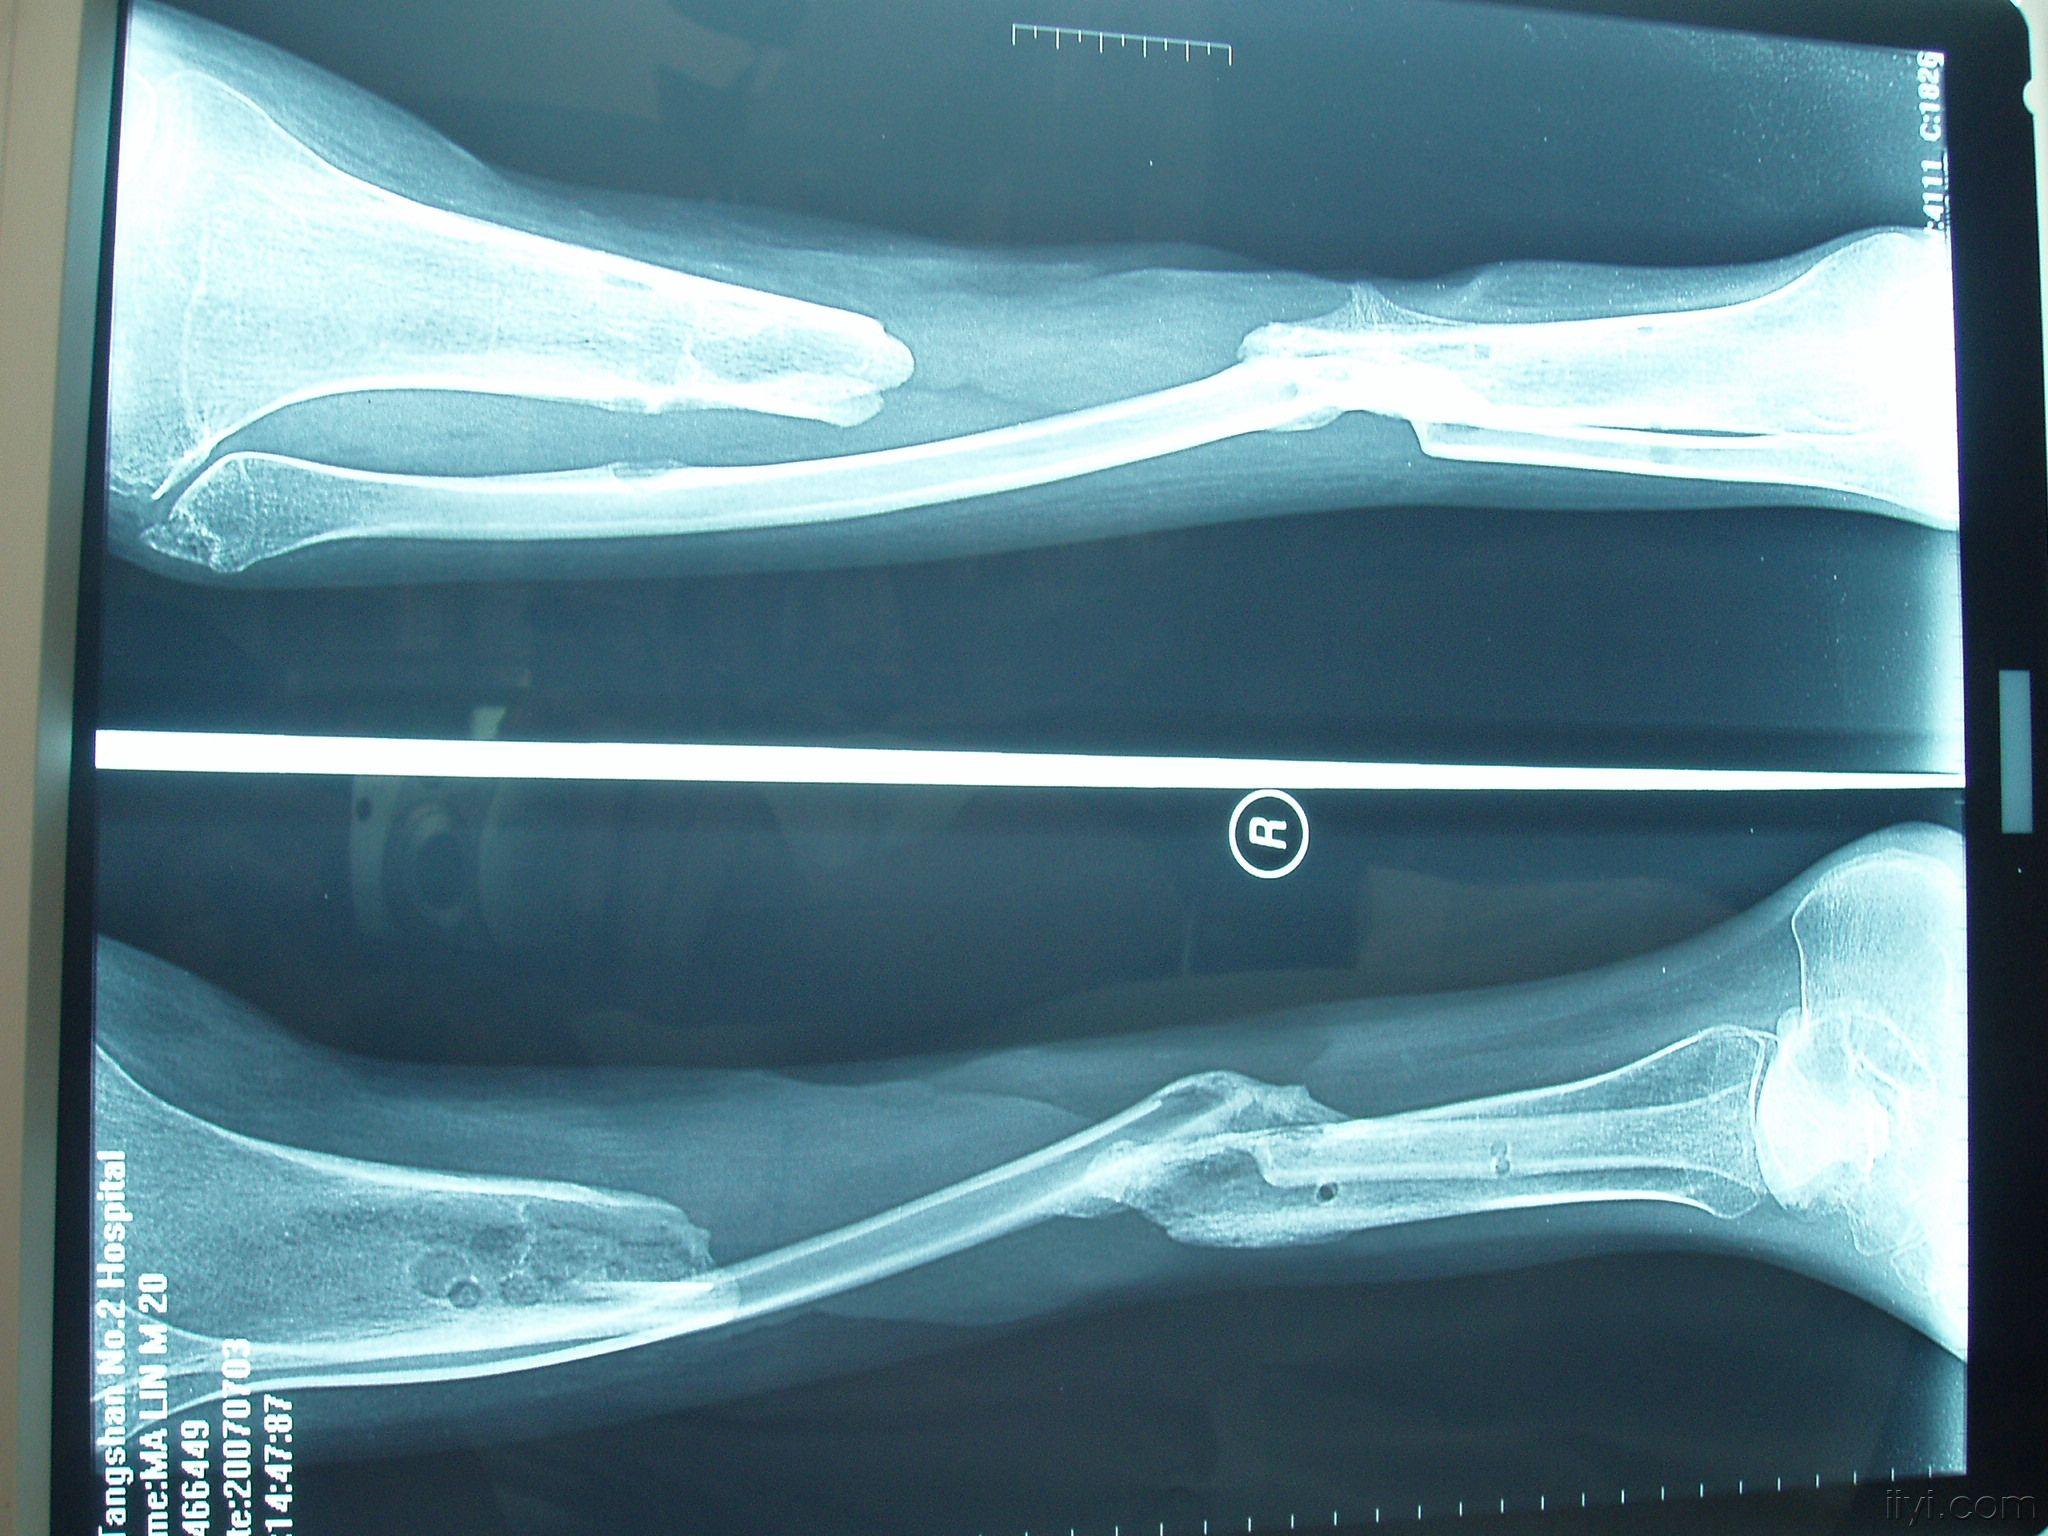

胫骨缺损------征求治疗方案 - 骨科与显微外科专业讨论版 - 爱爱医

图片尺寸2048x1536